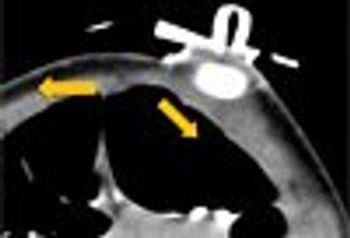

With the ability to more accurately diagnose acute injuries in the emergency department, it is no wonder that the use of computed tomography scanning has increased over the past decades.

The author recalls the first time she ordered a CT scan in the mid-1970s.